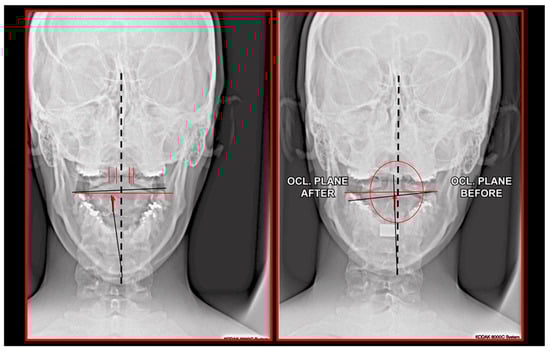

11.5. Axis and Atlas Derotation

11.6. Treatments Focused on Temporomandibular Joint

11.7. Treatment of Occlusion